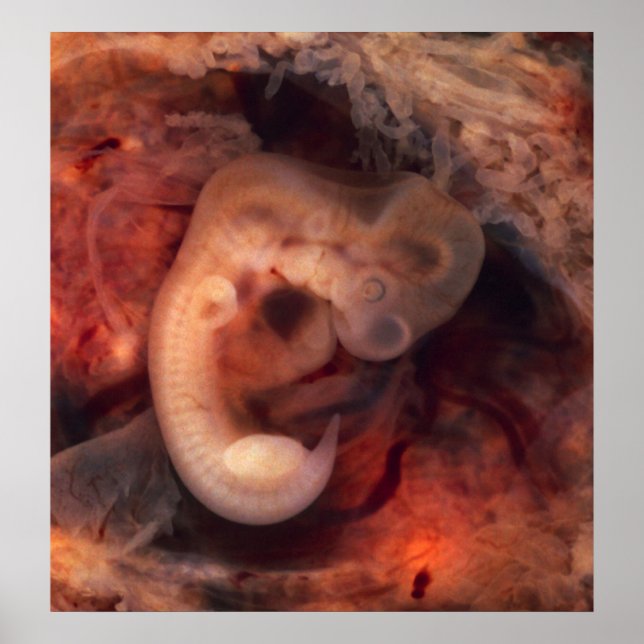

Embryo vom Menschen (7. Schwangerschaftswoche, 5. Dieses Foto eines geöffneten Oviduct mit einer ektopischen Schwangerschaft weist einen spektakulär gut erhaltenen 10-Millimeter-Embryo auf. Es ist ungewöhnlich, einen Embryo überhaupt in einem Ektope zu sehen, und für einen ist es ziemlich ungewöhnlich, dieses gut konservierte (und vom Messer des Prosektors ungestört) zu sein. Sogar ein Embryo dieser winzigen Generation weist sehr unterschiedliche anatomische Merkmale auf, wie Schwanz, Gliedmaße, Herzstück (das tatsächlich aus der Brust herausragt), Augenbecher, Hornhaut/Linse, Gehirn und eine deutliche Segmentierung in Somiten. Der Gestationssaal ist von einer Unzahl chorionischer Villen umgeben, die an längliche Party-Ballons erinnern. Dieser Embryo ist etwa fünf Wochen alt (oder sieben Wochen in dem biologisch irreführenden, aber sehr praxisorientierten, in der Geburtshilfe verwendeten verabredet System). Melden Sie sich kostenlos an und rettete 12% auf jede zazzle Bestellung zusätzlich zu einem $5.00 Anmelde-Bonus Alle Rechte vorbehalten; ohne Vorurteil, Rückgriff oder Benachrichtigung (U.C. 1-308) http://en.wikipedia.org/wiki/File:Tubal_Pregnancy_with_embryo.jpg Embryo schwangerer Schwangerschaft menschlichen Baby "menschlichen Embryo"